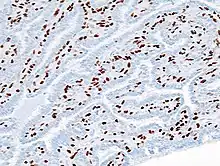

Histopathology of intraductal papilloma of the breast by excisional biopsy. Immunostaining for p63 protein.